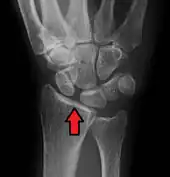

- Dynamic scapholunate instability visible upon clenching the wrist